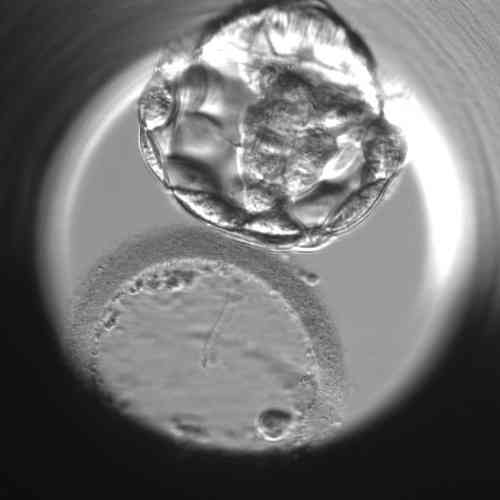

Am fünften Tag entwickeln sich die Embryonen bis zum Blastozystenstadium

Im Stadium der embryonalen Blastozyste sind die Zellen des Embryos bereits in den Embryoblasten (innere Zellmasse – ICM), aus dem der Embryo selbst entsteht, und das Trophoektoderm – Trophoblast, aus dem sich die Plazenta und die Amnionmembranen entwickeln, unterteilt. Im Inneren der Blastozyste befindet sich ein mit Flüssigkeit gefüllter Hohlraum, die Blastozele.

- Die expandierte Blastozyste, die ihr Gesamtvolumen bereits deutlich vergrößert, füllt den Embryo vollständig aus und die Embryohülle (Zona pellucida) wird allmählich dünner.

- Schlüpfende Blastozyste, deren Hülle (Zona pellucida) bei weiterem Volumenwachstum reißt und einige Zellen des Trophoectoderms nach außen wandern.

- Eine geschlüpfte Blastozyste (geschlüpfte Blastozyste), die die Hülle (Zona pellucida) vollständig verlassen hat und bereit ist, sich in der Gebärmutterschleimhaut einzunisten.